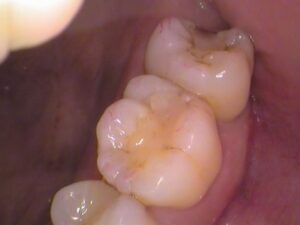

お口の中の状態

お口のを見てみましょう。

奥歯の歯の3本です。

5番目、6番目、7番目の歯があります。